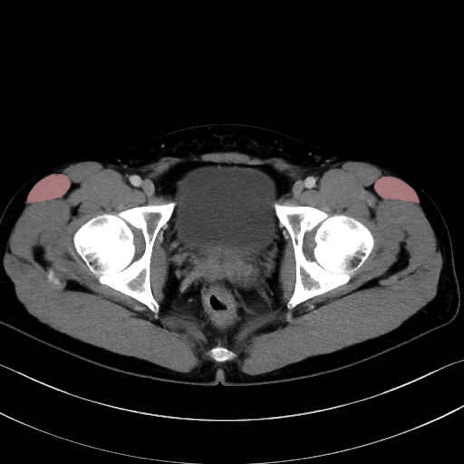

大腿筋膜張筋 (Tensor fasciae latae)